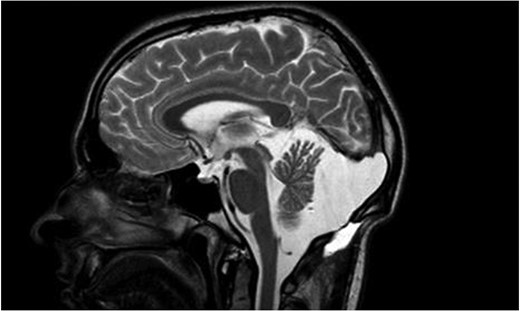

In this case, the radiological presentation was in favor of the diagnosis of a retrovermian arachnoid cyst and not a mega-cisterna magna (Fig. 1). This was further confirmed by the peroperative discovery of a typical arachnoid cyst with an arachnoid membrane, which was widely opened during cyst marsupialization.

Sagittal T2 weighted image showing a marsupialized retrovermian arachnoid cyst.